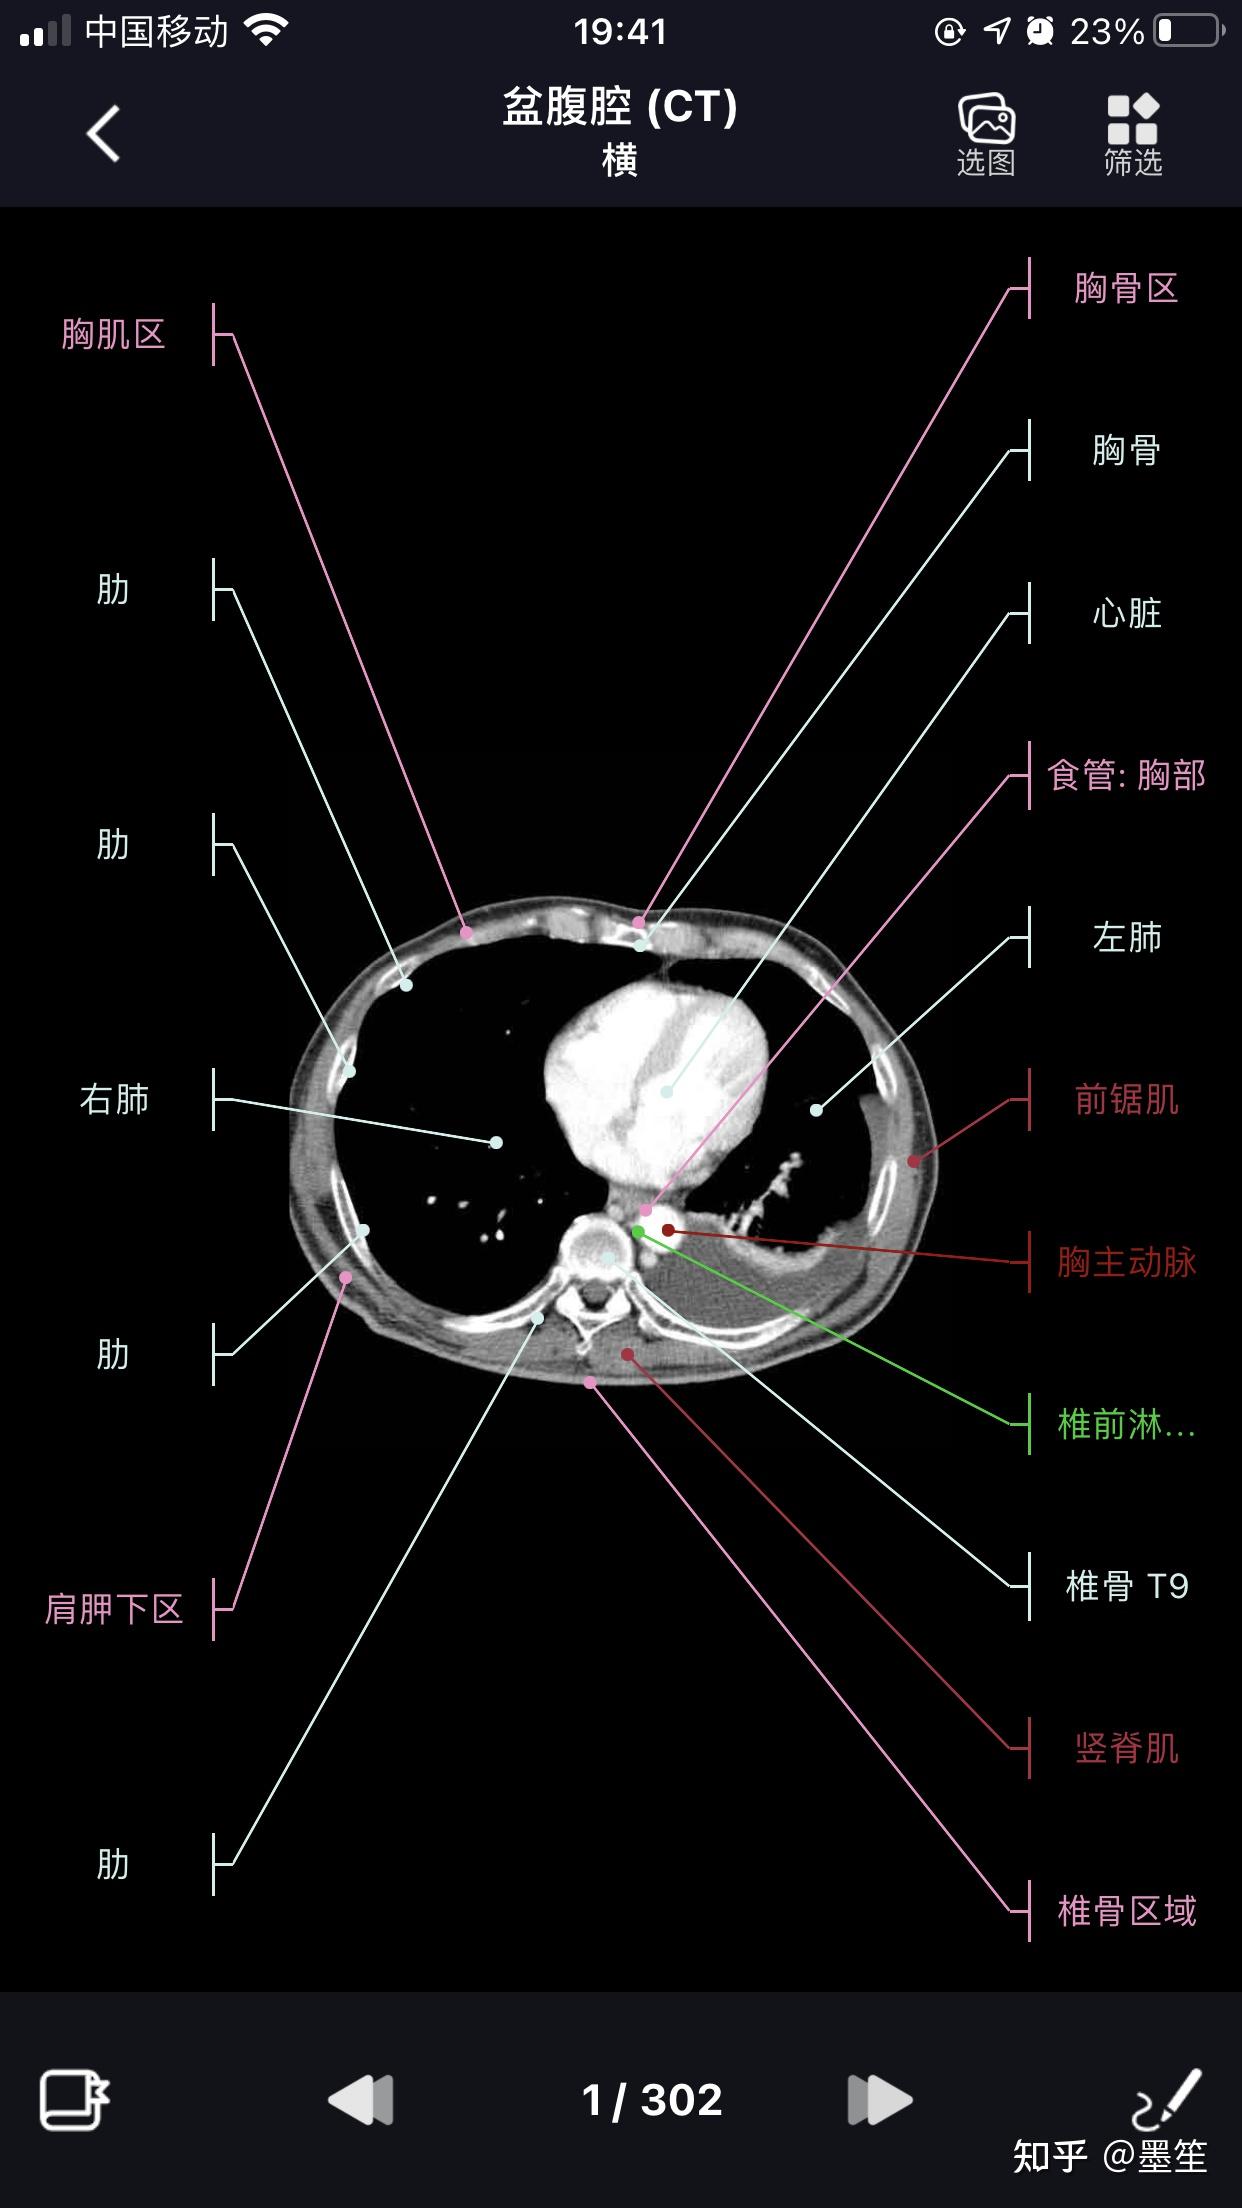

影像学习必备软件【影像解剖图谱】 - 知乎

图片尺寸1242x2208